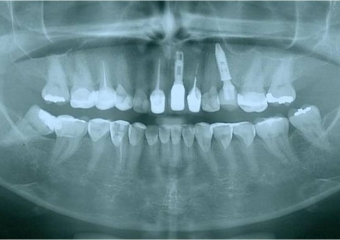

Raio X inicial com fratura radicular do dente 24